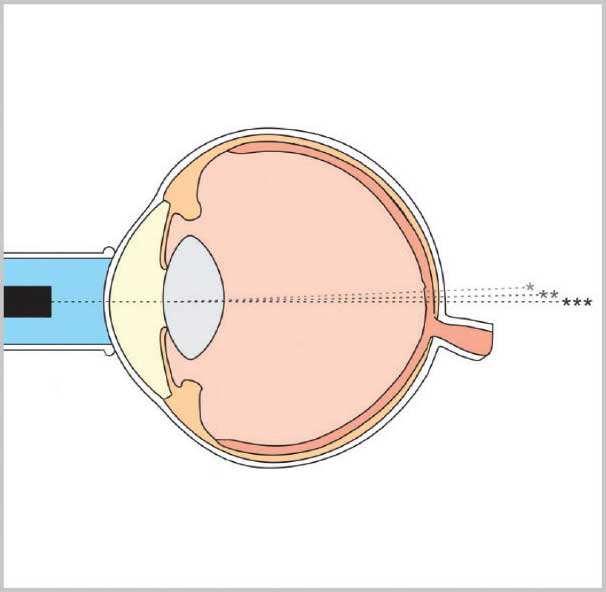

Унікальні функції керування вимірюванням Flex A-Scan допомагають досягти оптимальних значень вимірювань. Ці функції дозволяють користувачеві зосередитися на техніці застосування, в той час як програмне забезпечення приладу виконує аналіз форми хвилі в реальному часі і надає негайний зворотний зв'язок користувачеві.

Унікальний алгоритм оцінювання автоматично класифікує вирівнювання датчика вздовж осі вимірювання. Ранжування відбувається миттєво, і кожному якісному вимірюванню присвоюється 1 зірка, 2 зірки або 3 зірки (3 зірки означають найкраще вирівнювання).

Flex A-Scan може працювати в контактному або занурювальному режимі. Датчик випускає ультразвукові імпульси у воду (а не безпосередньо в око). Імпульси поширюються через воду і потрапляють у тканини. Цей метод вимірювання усуває потенційну деформацію геометрії рогівки, спричинену прямим контактом з датчиком.